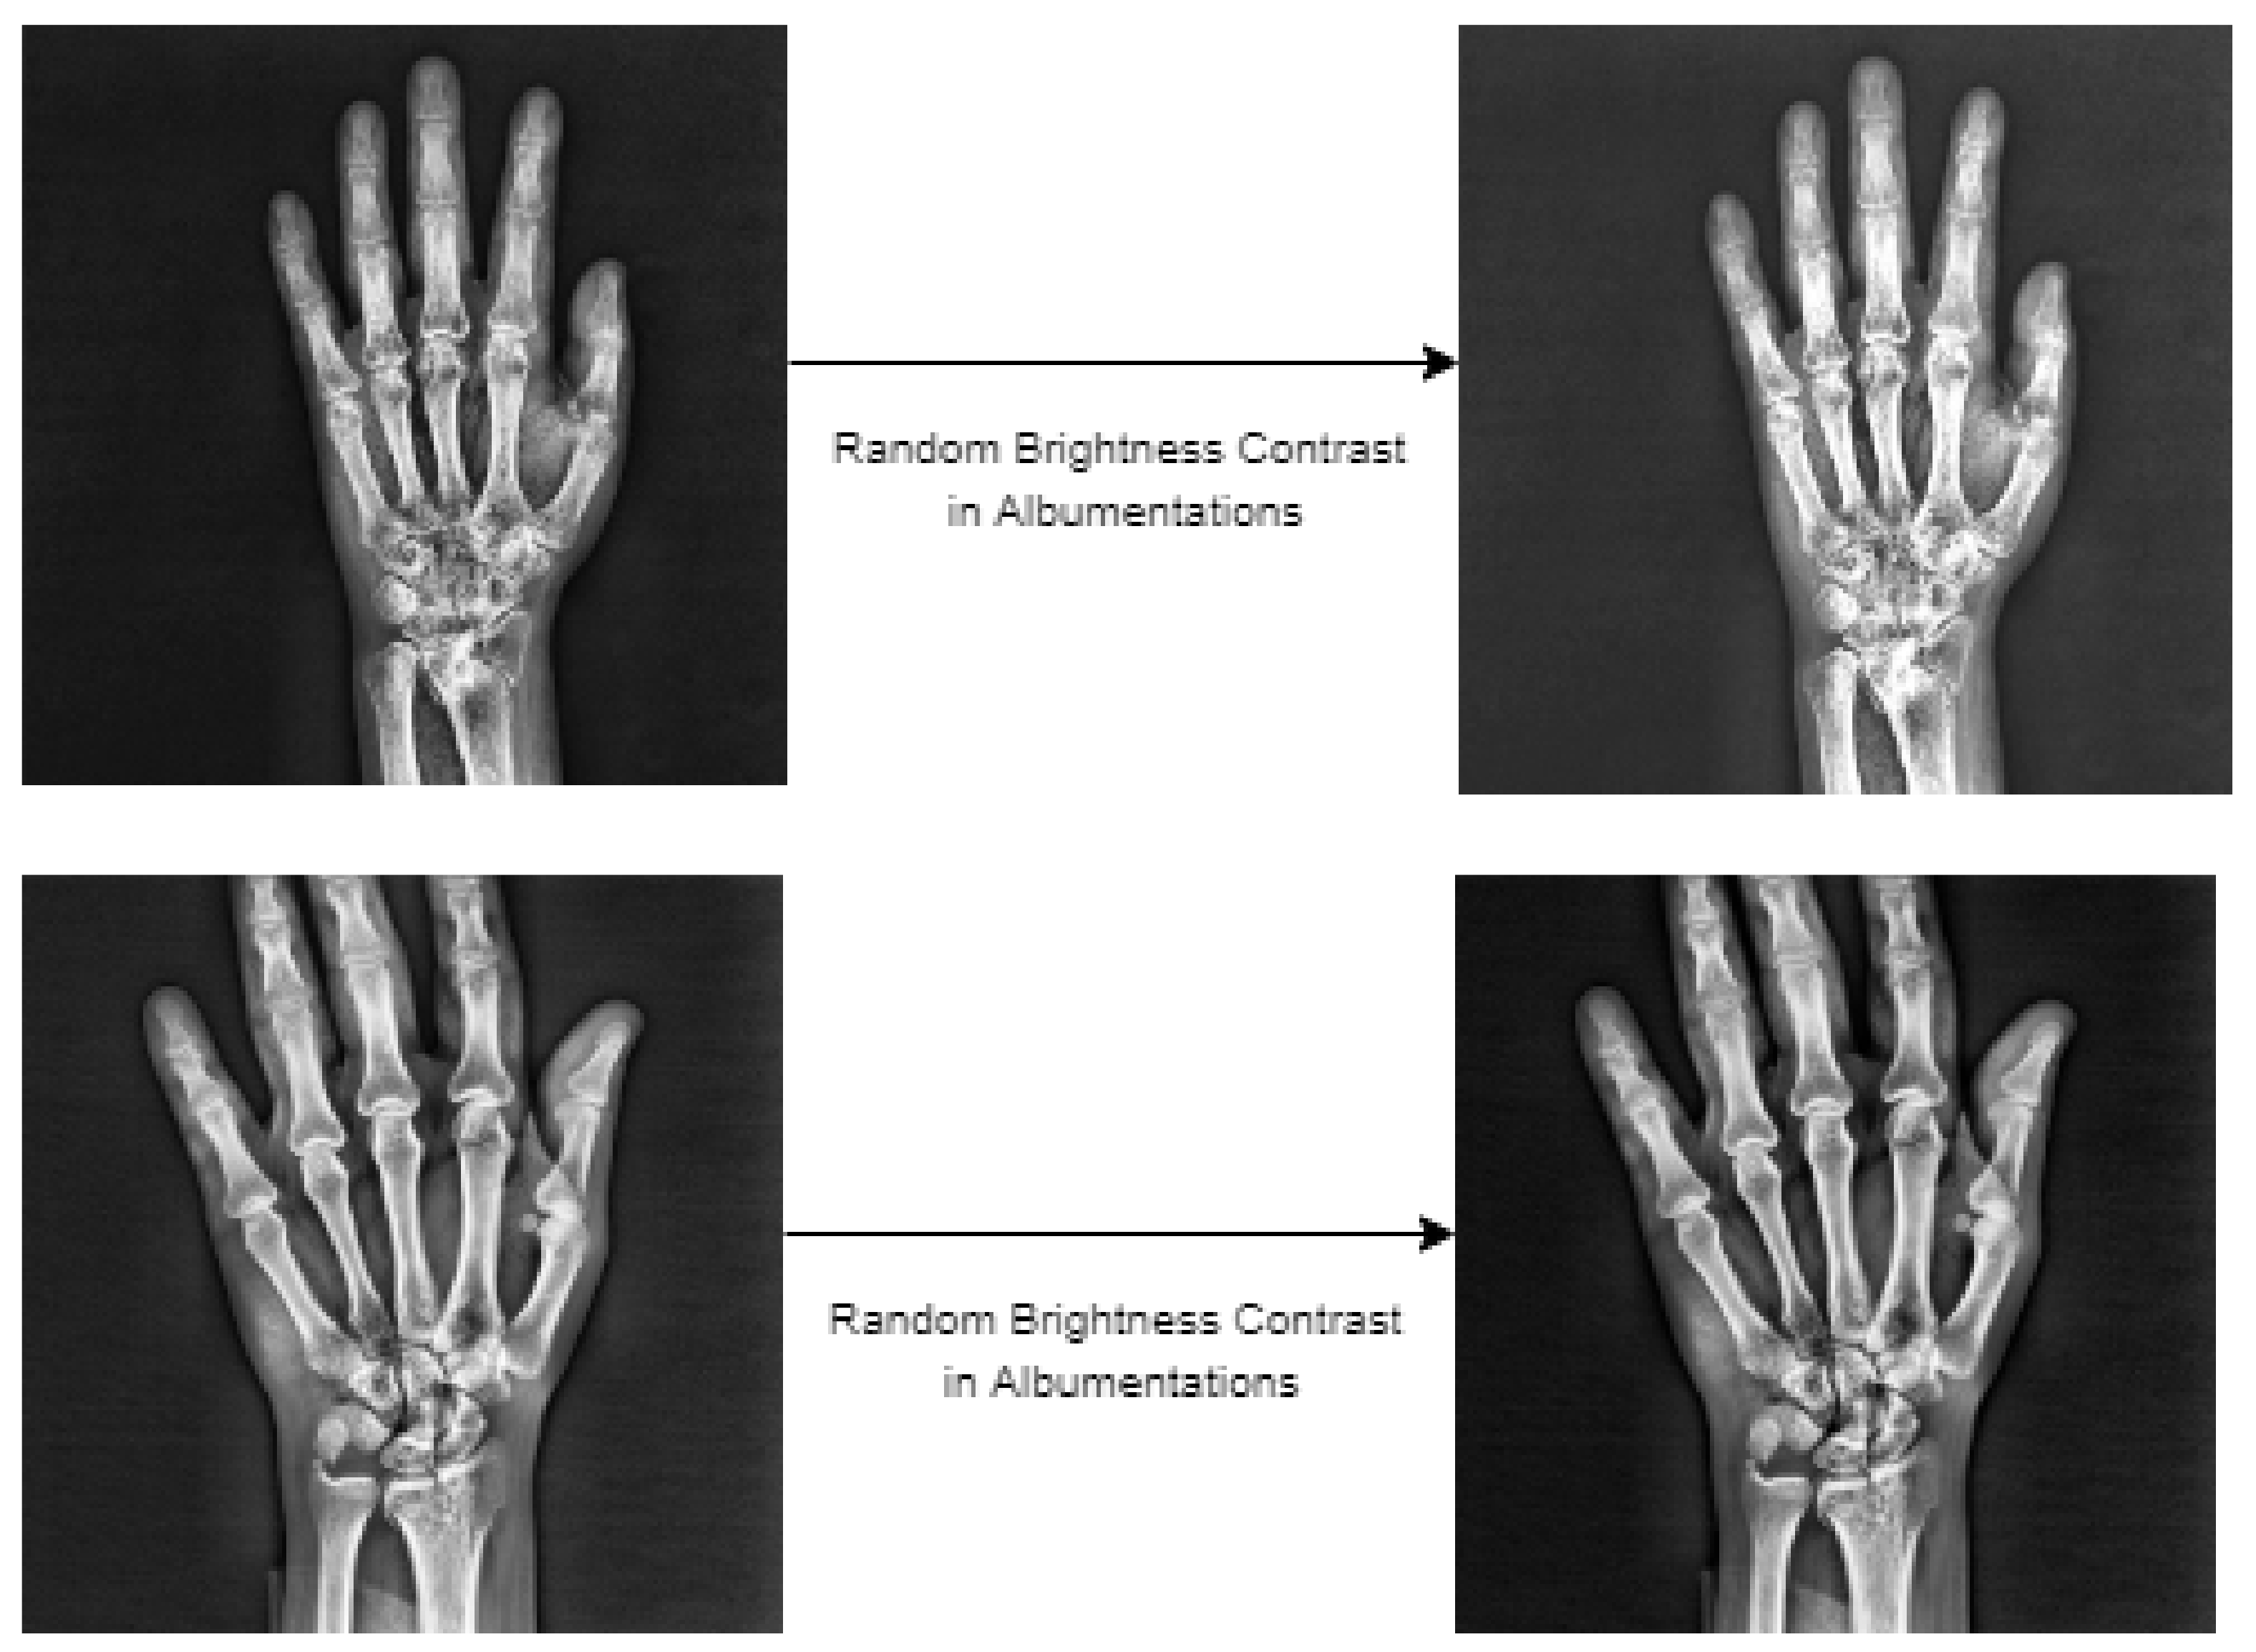

4.3. Data Augmentation of Wrist X-ray Images

The amount of data is essential for network training with deep-learning-based object detection models. Therefore, data augmentation was performed within the scope of this study in order to make the best of network training and to achieve high scores for fracture detection. As for the initial dataset, various augmentations were tried using the Albumentations [37] library. Albumentations is a flexible and fast image augmentation python library that can be used in different computer vision tasks that include object detection, classification and segmentation, which are particularly deep-learning-based open source projects [37]. In augmentations performed using this library, random brightness contrast, sharpness, noise, gamma, gaussian blur and median blur were used. Experiments of augmentation were conducted using these six different methods used in these procedures, either individually or together. Upon analysis of the detection procedures performed with augmentation, methods that have a negative impact on the result of detection, methods with no impact or the methods inclined to augmentation were identified. Based on the experiments, it was concluded that random brightness contrast augmentation made the greatest contribution for detection of fractures in the Albumentations library. This type of augmentation was used in addition to the random flip ratio 0.5 augmentation available in the training stage of the models in the MMdetection tool used for detection. Samples of the images obtained as the result of the augmentation steps are presented in Figure 12 below.

Figure 12.

The wrist X-ray images after data augmentation.